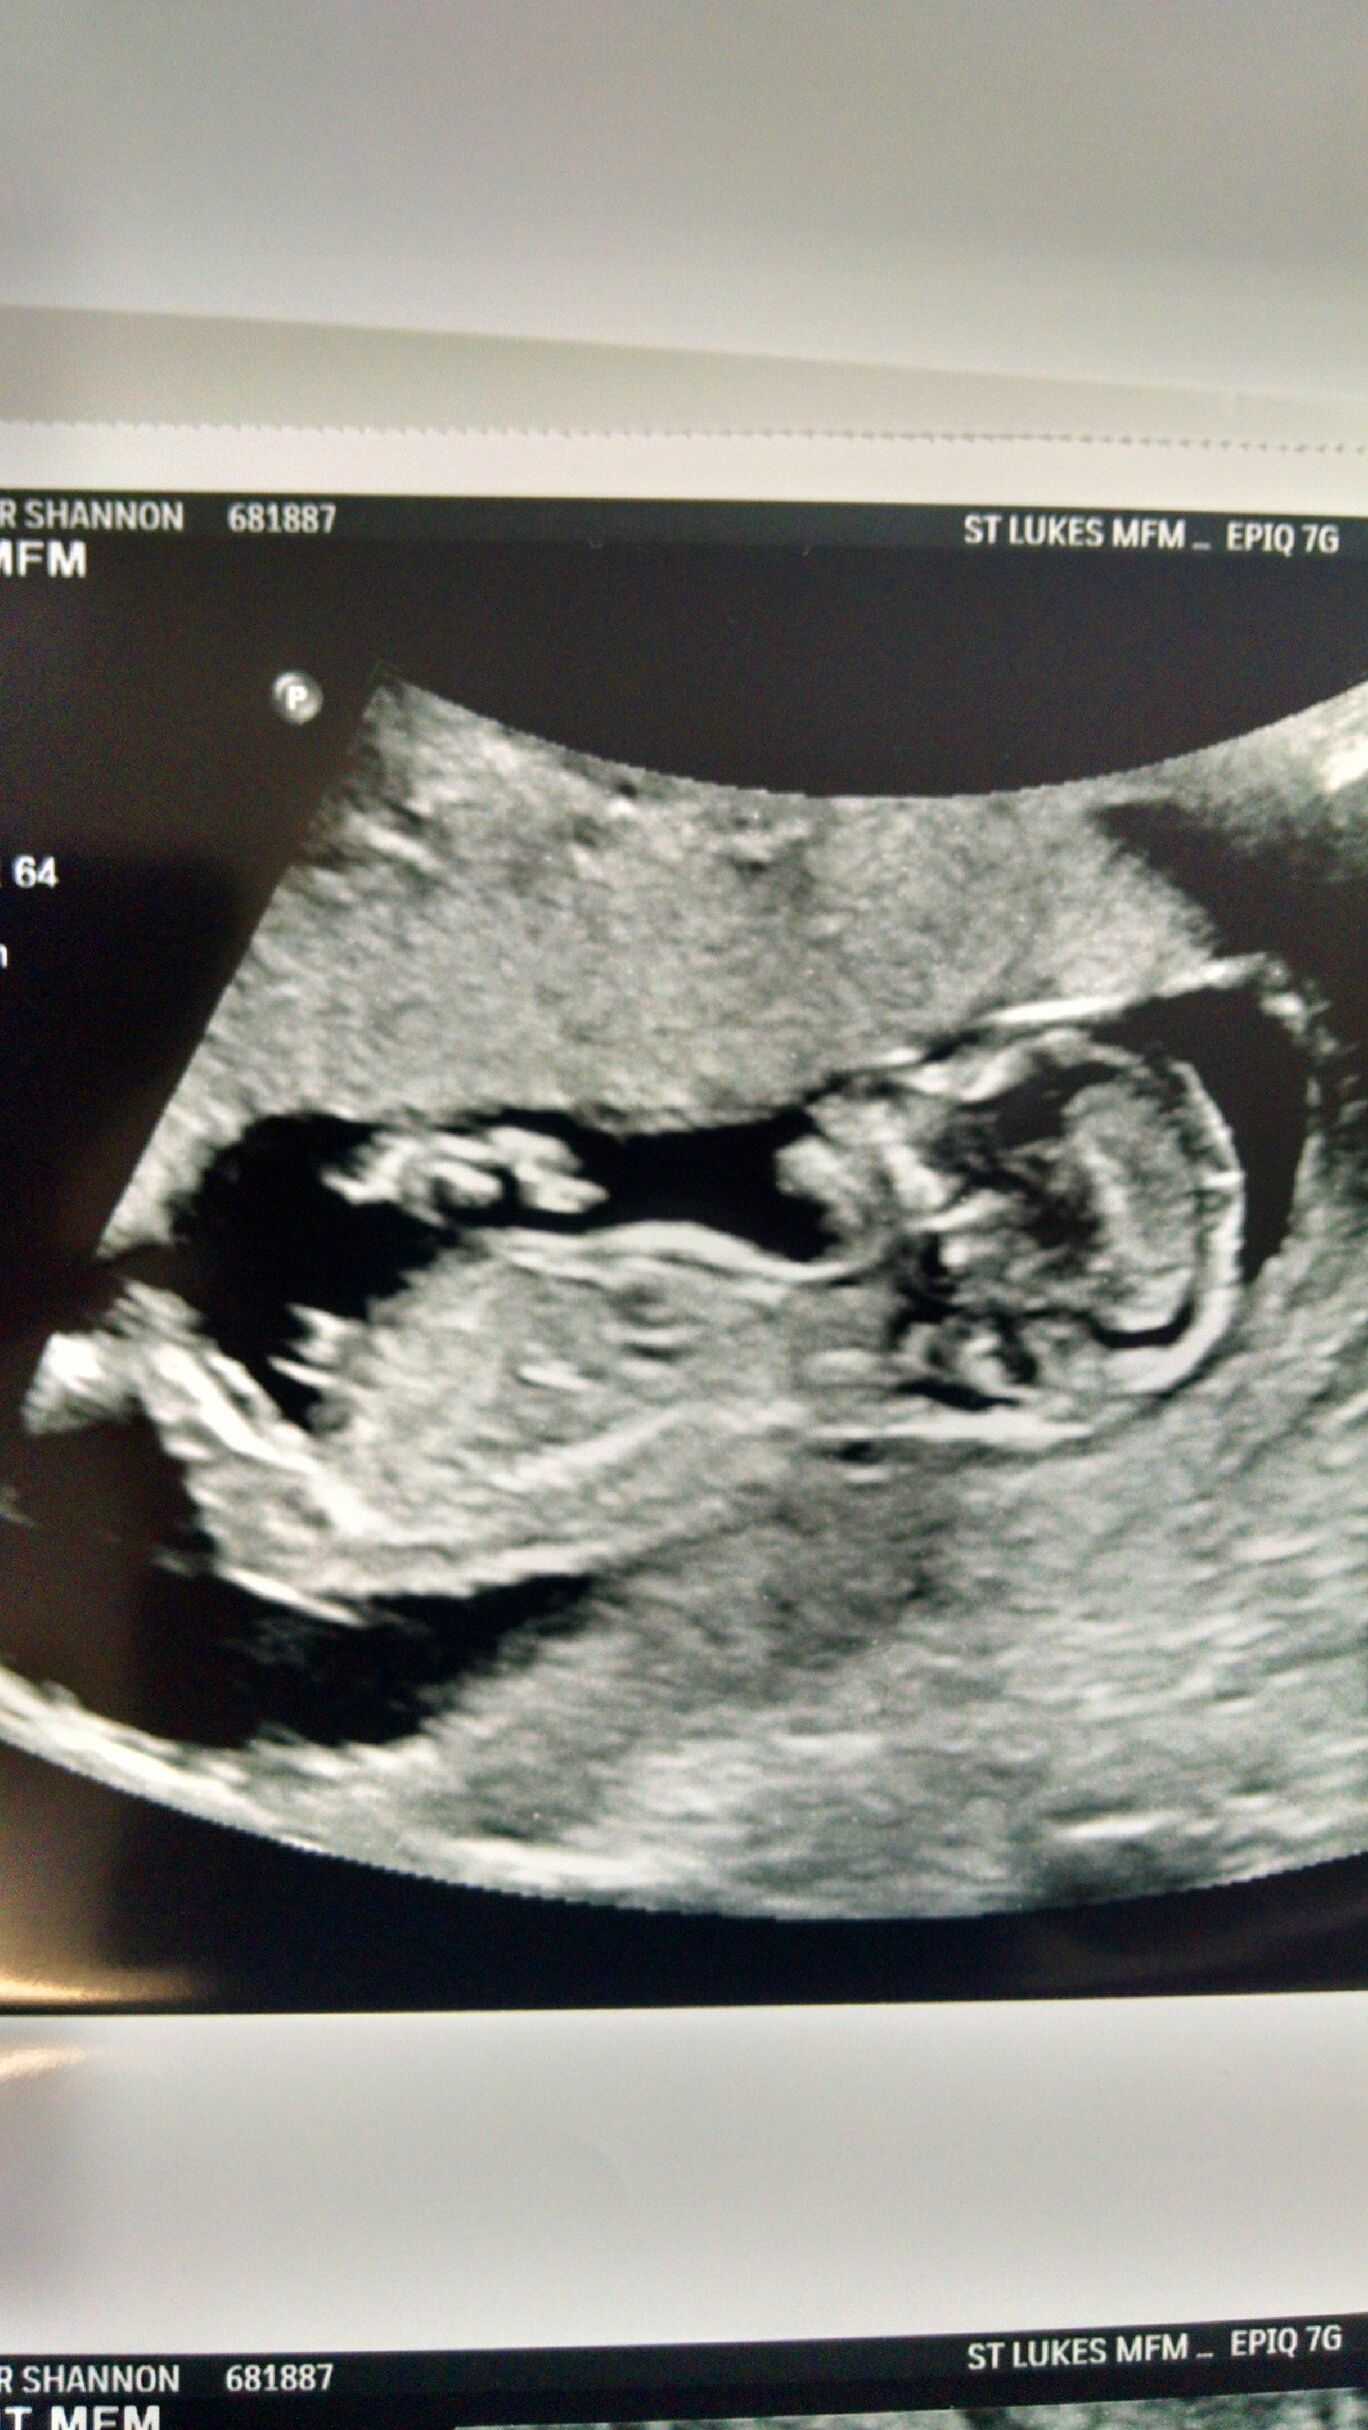

I am not sure if this is a nub or not. But here are my 13w scan pics. Any and all guesses welcome. These are all the pics I got and no video. :)

Attachment 36130

Baba's leg is hiding the nub. Super cutie though! :heart: did you see any clues during the scan? X

NONE!!! Little one was not cooperating at all and would not move in the right directions for us. And she had it zoomed in on the head most of the time. I guess I am still officially team GREEN!!! :) :)

not getting a good feel from these either way - 50-50 from me! Beautiful baby!!